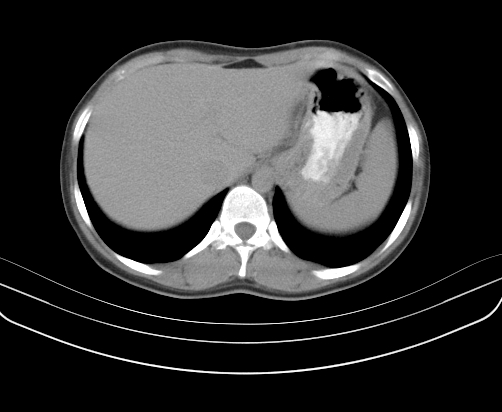

静脉期